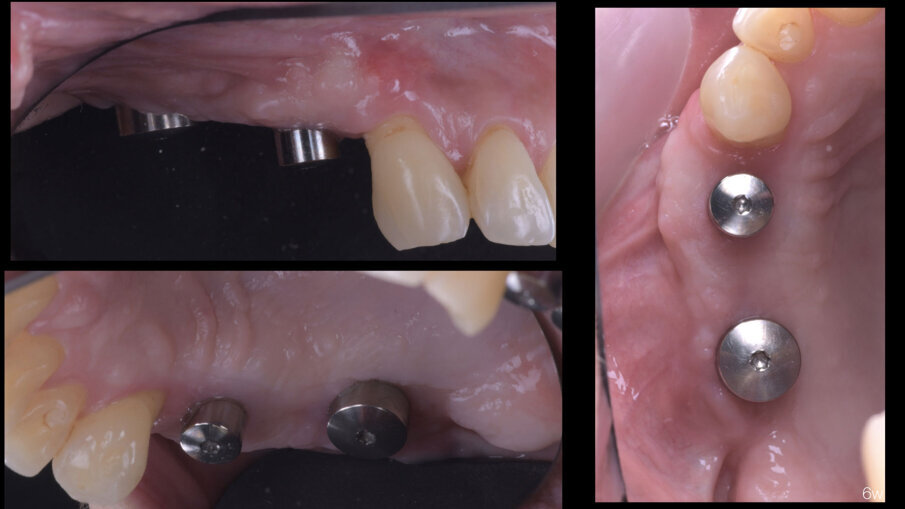

A distanza di 6 mesi, previa acquisizione di una CBCT (Figg. 8-10), si procede con il rientro chirurgico nella sede ricostruita (Fig. 11). Scheletrizzato il mascellare ricostruito, si riscontra una parziale risoluzione del difetto verticale in sede 1.5 e il ripristino di volumi ossei idonei all’inserimento di impianti in posizione protesicamente guidata in sede 1.4 ed 1.6. Durante la preparazione dei letti implantari, si esegue il prelievo di due carote ossee mediante fresa trephine da 3.3 mm. Segue quindi l’inserimento di due impianti Tissue Level SP 4.1 x 8 mm (Straumann) e l’adozione di un protocollo di guarigione sommerso (Figg. 12, 13).

Fig. 12 - Prelievi bioptici ed inserimento implantare.

Fig. 13 - Chiusura per prima intenzione e sommersione impianti.

A distanza di 3 mesi, si procede alla seconda fase implantare abbinata a una vestiboloplastica, col fine di ripristinare la profondità del fornice vestibolare ed un’idonea anatomia dei tessuti molli perimplantari (Figg. 14, 15). Le biopsie del tessuto osseo prelevate in fase di inserimento implantare sono state processate con tecnica standard, non decalcificata, e colorate con blu di toluidina e pironina gialla.

Fig. 16 - Guarigione clinica a 6 settimane.